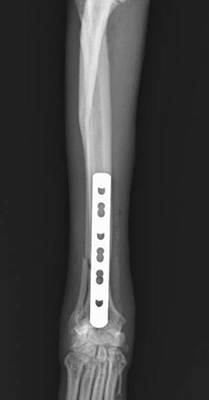

当院では前十字靭帯断裂の手術『TPLO(脛骨高平部水平化骨切り術)』を実施することが可能です。

脛骨の骨切りを行い、脛骨高平部の傾斜を水平になるように矯正する手術です。

残存靭帯の保護効果が唯一文献的に証明された術式で、特に中型犬以上の体格の子では従来の手術方法に比べて改善率が良いです。